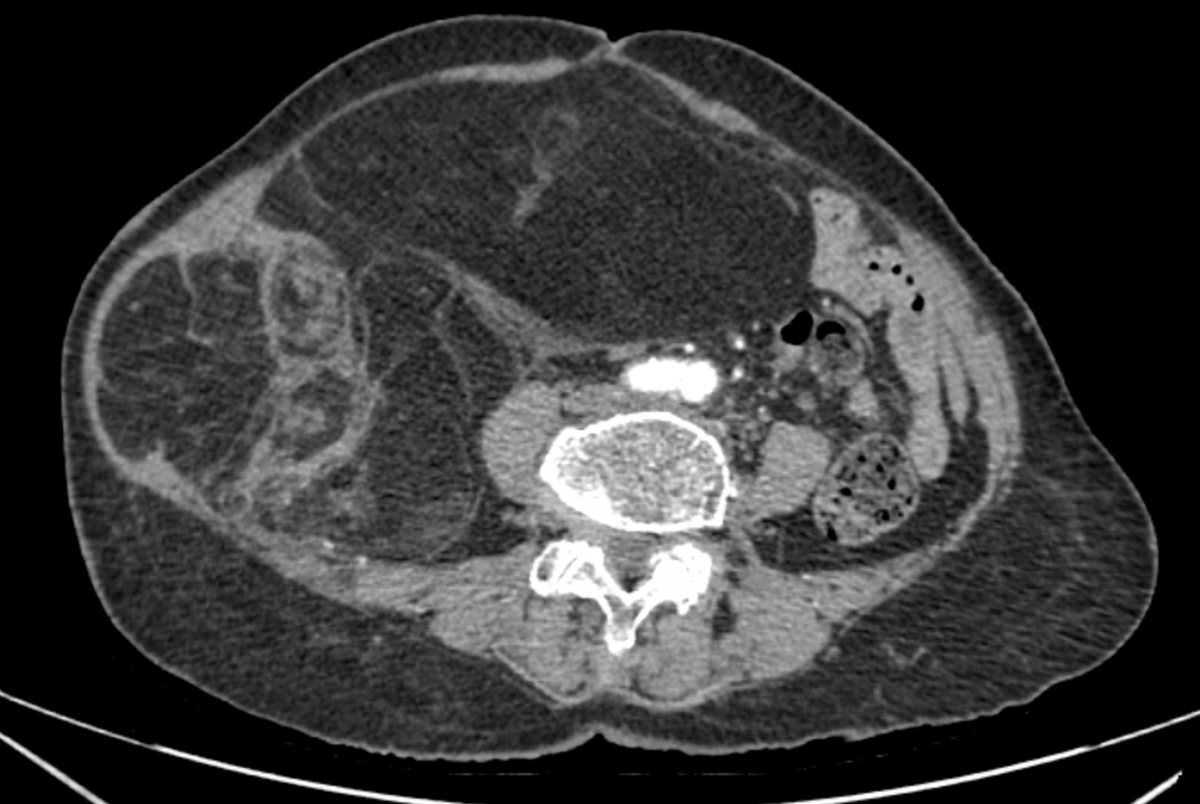

Bệnh nhân N.T.T, 76 tuổi nhập viện do bụng to nhanh, căng tức, biến dạng vùng hạ sườn – mạn sườn phải trong khoảng ba tháng gần đây. Chẩn đoán hình ảnh (CT ổ bụng có thuốc cản quang) cho thấy khối choán chỗ sau phúc mạc, kích thước 28 × 15 cm, cấu trúc hỗn hợp tổ chức mỡ – đặc , đè đẩy tạng trong ổ bụng nhưng không có dấu hiệu xâm lấn các tạng lân cận. Kết hợp lâm sàng và hình ảnh học, bệnh nhân được chẩn đoán sarcoma mỡ sau phúc mạc.